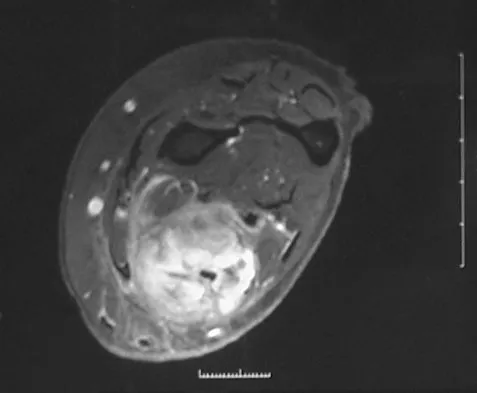

A 37-year-old woman has had intermittent paresthesias and numbness in the plantar foot for the past 6 months. She reports that the symptoms are worse with activity, and the paresthesias are beginning to awaken her at night. MRI scans are shown in Figures 6a and 6b. What is the most likely diagnosis?

Explanation

The symptoms are consistent with tarsal tunnel syndrome. Ganglion cysts are a well-known cause of tarsal tunnel syndrome. The MRI scans show a high intensity, well-circumscribed mass in the tarsal tunnel that is consistent with a fluid-filled cyst. Patients usually respond well to excision of the ganglion and resolution of the tarsal tunnel symptoms. The surrounding fat is a different signal intensity on the MRI scans, which rules out a lipoma. Synovial cell sarcoma has a heterogeneous appearance on an MRI scan. Metastatic tumors are most commonly found in the osseous structures of the foot, not the soft tissues. Rozbruch SR, Chang V, Bohne WH, et al: Ganglion cysts of the lower extremity: An analysis of 54 cases and review of the literature. Orthopedics 1998;21:141-148. Llauger J, Palmer J, Monill JM, et al: MR imaging of benign soft-tissue masses of the foot and ankle. Radiographics 1998;18:1481-1498.